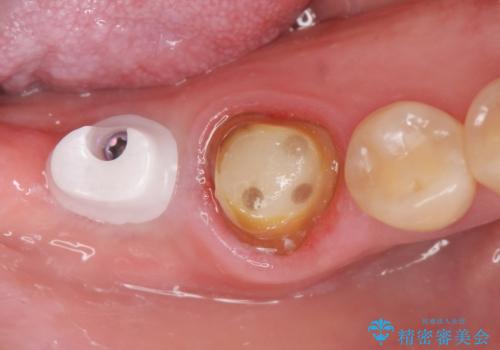

咬合機能を回復する奥歯のインプラント治療

- 失った右下最後方臼歯の咬合機能の回復を求めてインプラント治療を希望され来院されました。

インプラントを埋入するのに十分な骨の量がCT検査により確認されたので、インプラントによる治療を計画します。

- 44万円(インプラント・ジルコニアカスタムアバットメント・ジルコニアクラウン・仮歯)費用は治療当時の料金となります